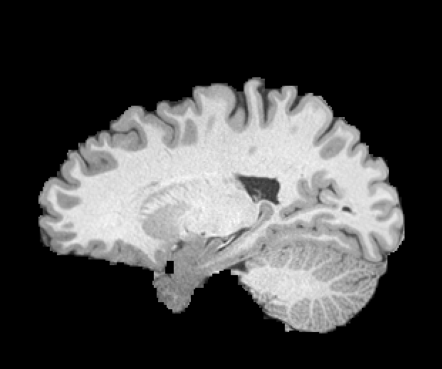

Inverse consistent rigid, affine, nonparametric, and MLP registration. We train networks on MNIST 5s using the methods in Secs. 3 and 4, demonstrating that the resulting networks are inverse-consistent. Our TwoStepConsistent (TSC) operator can be used on any combination of the networks defined in Sec. 3. For demonstrations, we join an MLP registration network to a vector field registration network, and join two affine networks to two vector field networks. Fig. 2 shows successful inverse-consistent sample registrations.

| Moving Image | Warped Image | Fixed Image | Moving Image | Warped Image | Fixed Image |